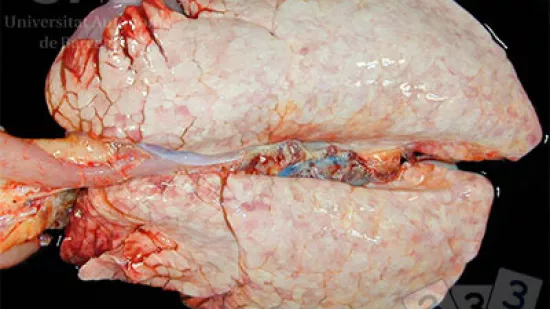

Die beobachteten Lungenveränderungwn werden verursacht durch…